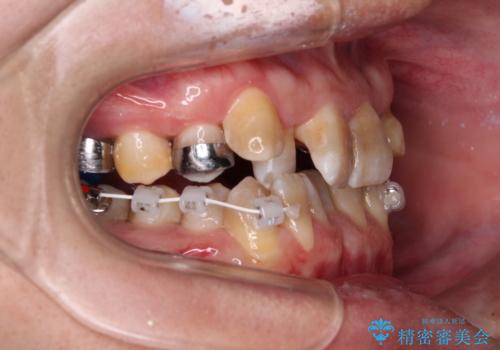

- 上下の前歯のデコボコを改善したいと来院された患者様です。

上顎の歯列幅が狭く、それによって歯が並ぶスペースが不足しています。

また下顎の歯列幅も制限され、内側に歯が倒れています。

それらを改善するため上顎に拡大装置を用いて、審美装置にてワイヤー矯正を行いました。

左上の乳犬歯は当初保存する計画でしたが、虫歯が大きいため抜歯になり、患者様の希望によりブリッジにしました。